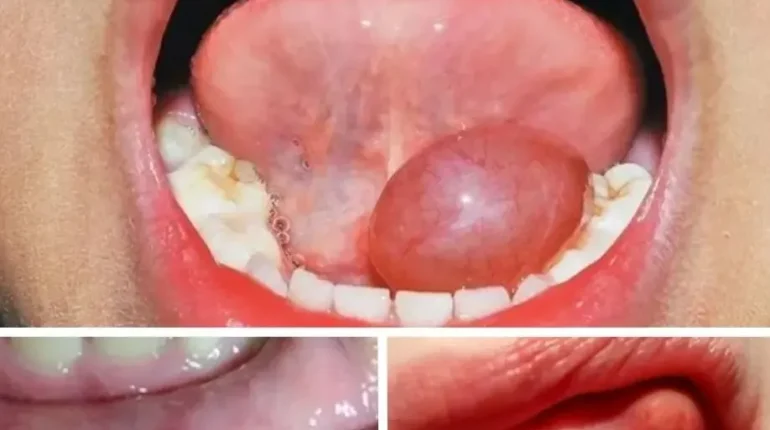

📌 These 7 Mouth Changes Could Signal Something Far More Serious Than You Think

Your mouth can reveal dangerous truths. Seven changes—from persistent sores to unexplained numbness—may signal oral cancer, a disease affecting over 77,000 Indians annually. Early detection transforms survival rates from 27% to 82%, making awareness your strongest defense.